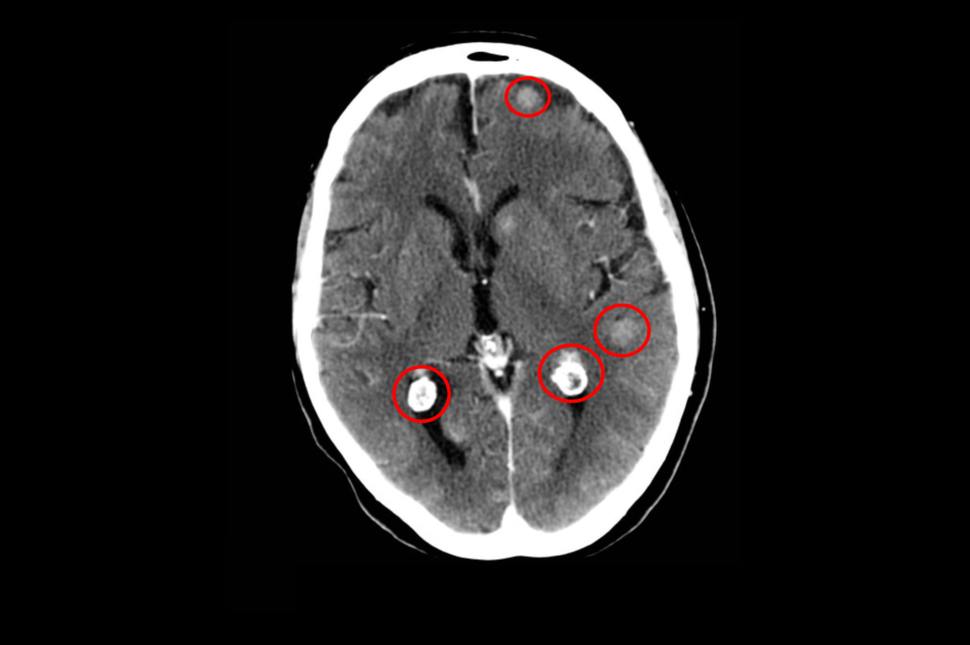

In addition, for patients whose lung cancers had spread to the brain, lorlatinib reduced the risk of their tumors progressing and helped prevent new brain metastases better than crizotinib.

The drug’s ability to reach the brain is important because ALK-positive lung cancers tend to spread to the brain. In fact, up to 40% of people with the disease develop brain metastases within 2 years of being diagnosed.

About 25% of CROWN trial participants had brain metastases when the study began. At 5 years of follow-up, the disease had progressed in only 8% of the patients with brain metastases treated with lorlatinib but in 79% of those treated with crizotinib.

Among the 114 participants in the lorlatinib group who did not have brain metastases when the study began, only four participants went on to develop brain metastases. These results suggest that the drug can not only control but also help prevent brain metastases, the researchers wrote.